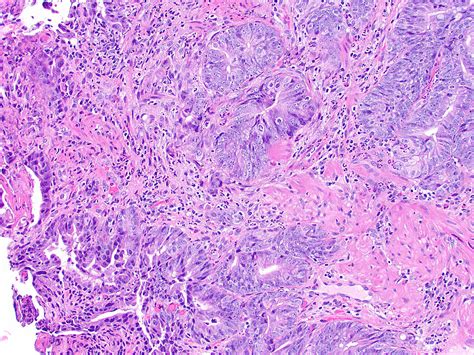

High Grade Dysplasia refers to abnormal changes in the cells lining the esophagus. These changes are more severe than those seen in low-grade dysplasia and indicate a higher risk of developing esophageal cancer. Barrett's esophagus, a condition where the normal cells lining the esophagus are replaced by cells similar to those found in the intestine, is a common precursor to high-grade dysplasia.

• Biopsy: During an endoscopy, tissue samples are taken from the esophagus and examined under a microscope to detect abnormal cells.

High-Grade Dysplasia Severe abnormal changes in the cells. High